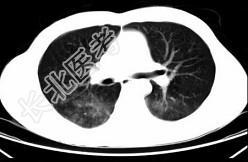

- 单项选择题男,35岁, 被车撞伤后1小时,结合影像图像选择其最可能的诊断为 ( )

D、肺挫伤